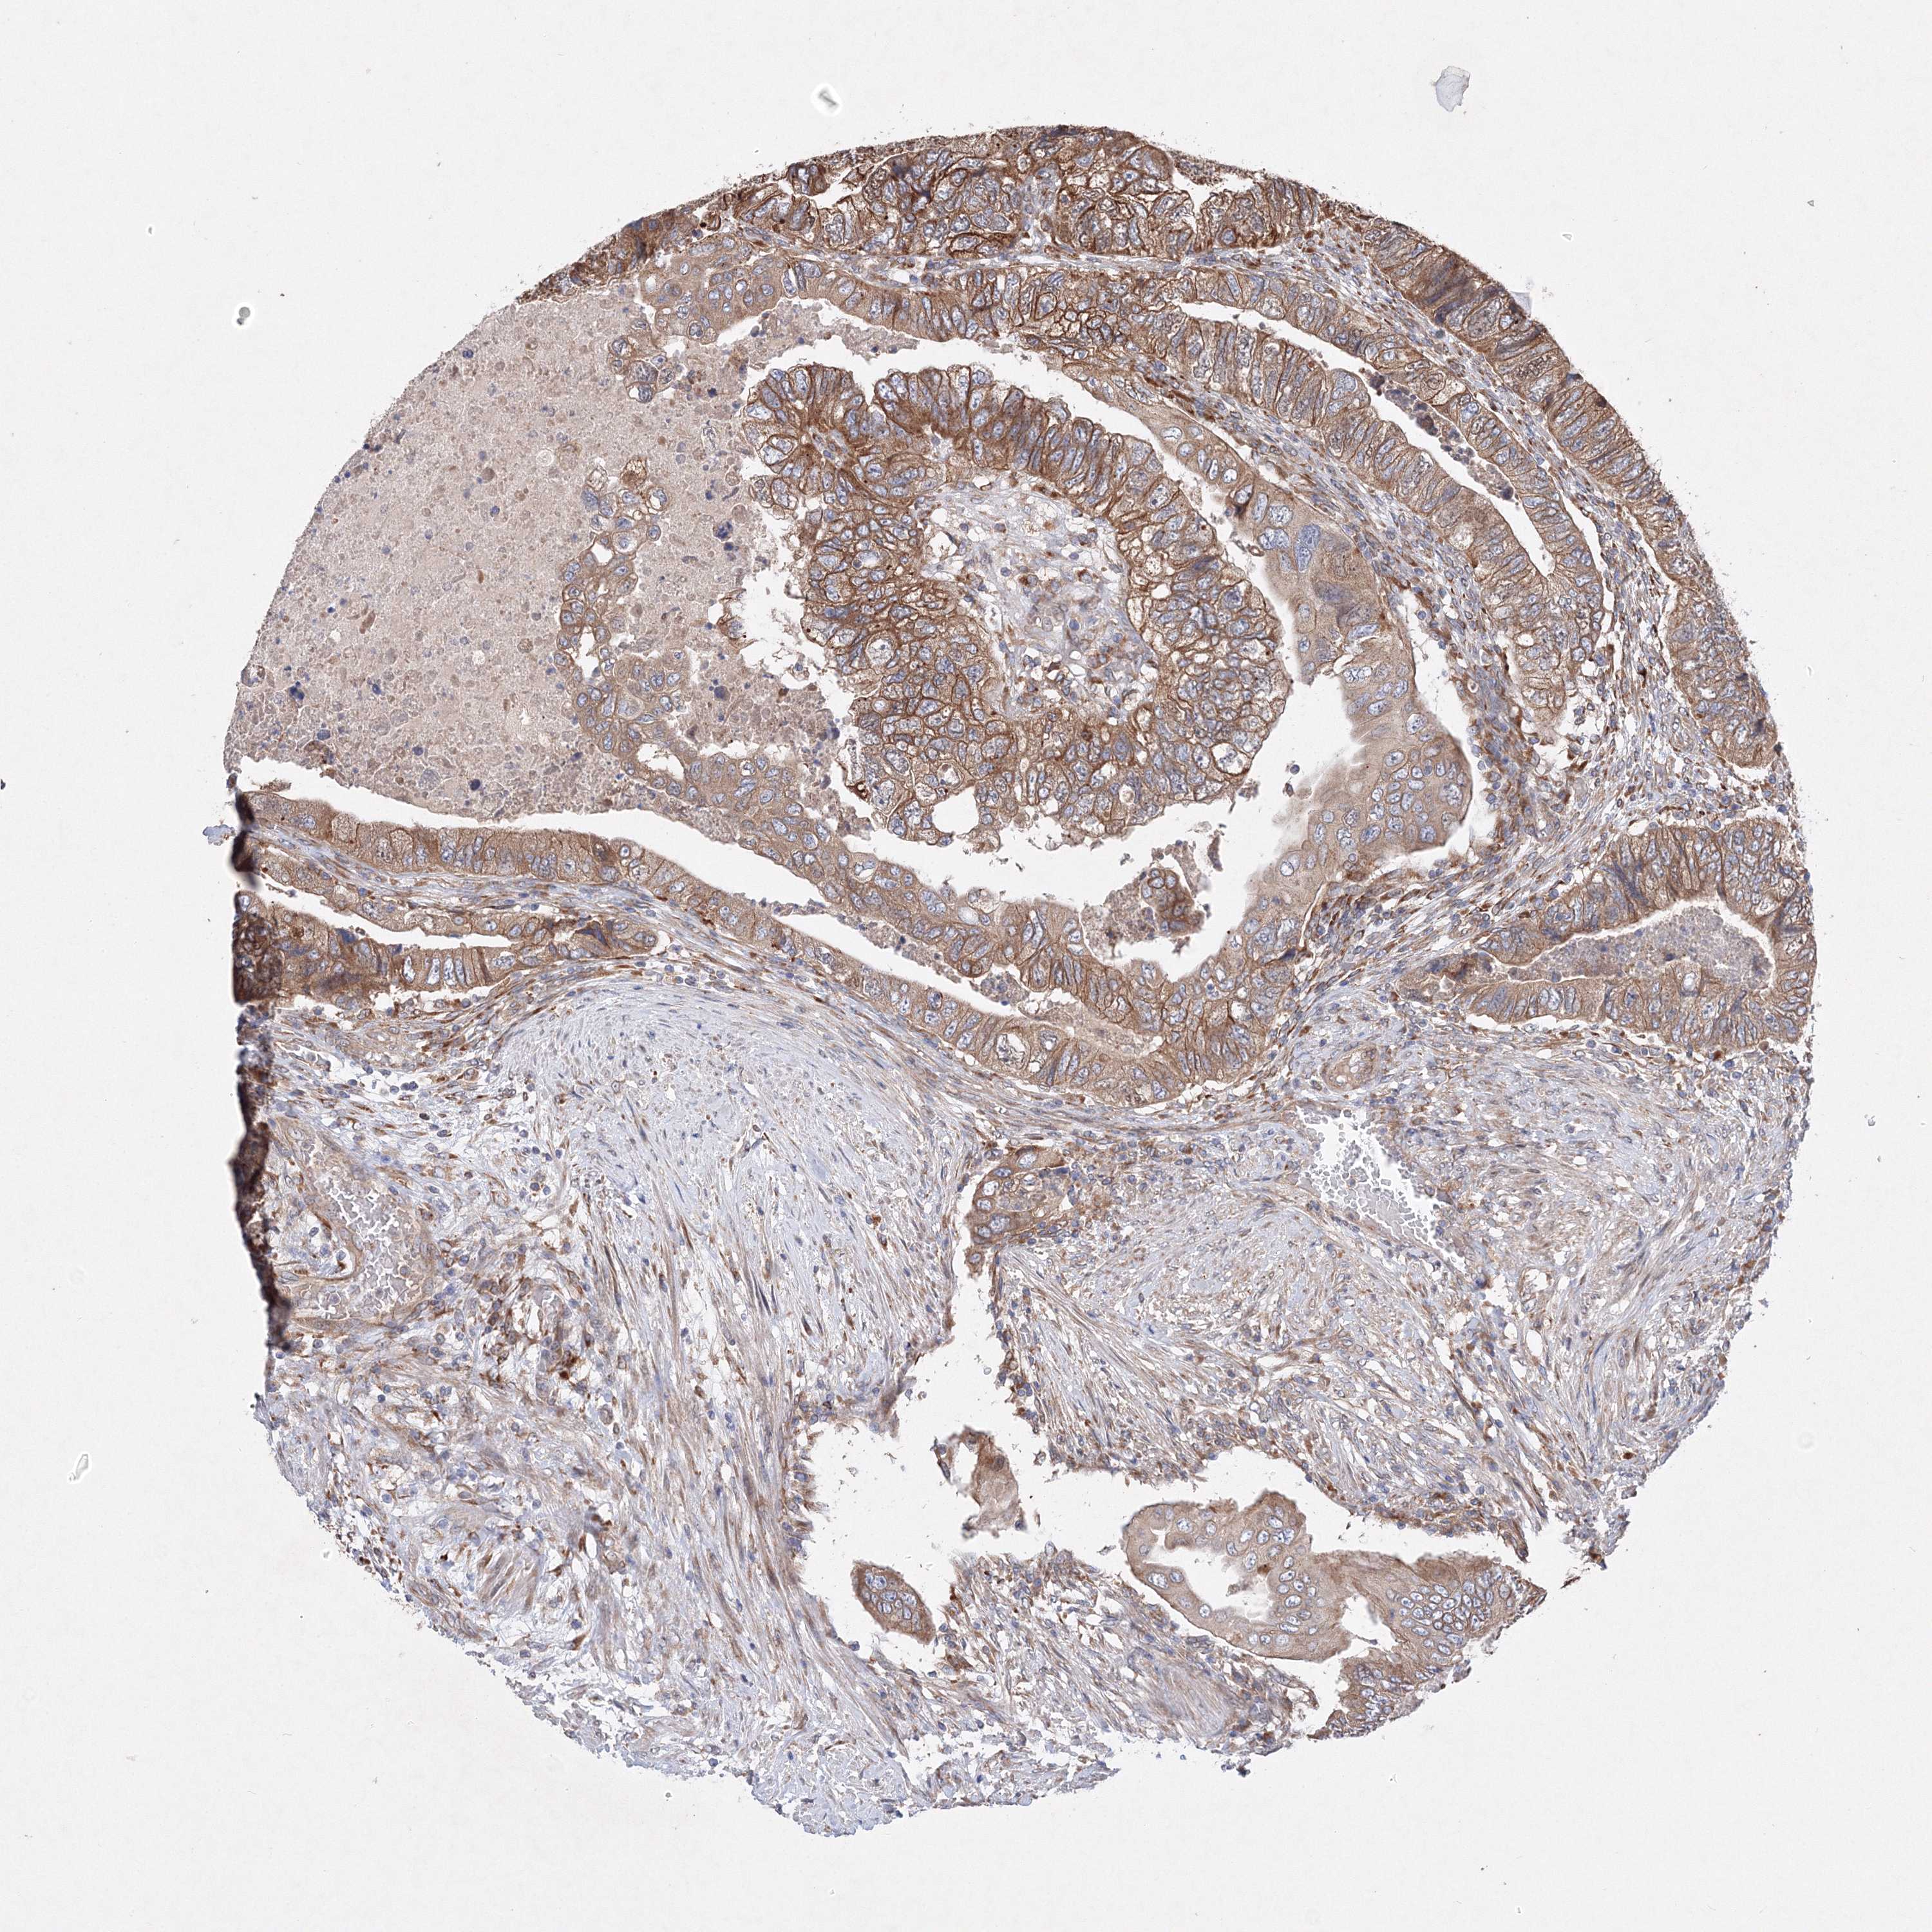

CANCER COLORECTAL CANCER Show tissue menu

Colorectal cancer

Human cancer

Colon adenocarcinoma

Rectum adenocarcinoma